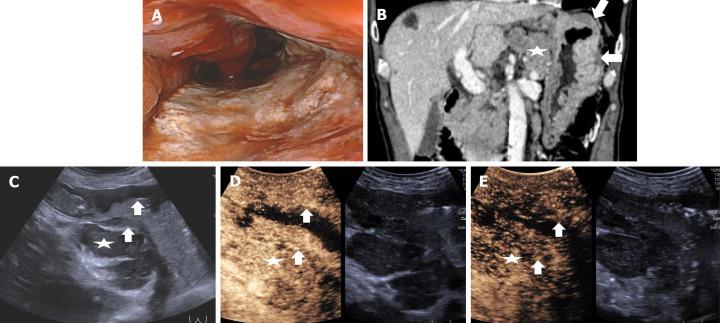

This single prospective study enrolled patients with GC confirmed by preoperative gastroscopy from July 2021 to March 2023. Patients underwent DCEUS, including ultrasonography (US) and intravenous contrast-enhanced ultrasonography (CEUS), and MDCT examinations for the assessment of preoperative T staging. Features of GC were identified on DCEUS and criteria developed to evaluate T staging according to the 8 edition of AJCC cancer staging manual. The diagnostic performance of DCEUS was evaluated by comparing it with that of MDCT and surgical-pathological findings were considered as the gold standard.

A total of 229 patients with GC (80 T1, 33 T2, 59 T3 and 57 T4) were included. Overall accuracies were 86.9% for DCEUS and 61.1% for MDCT ( < 0.001). DCEUS was superior to MDCT for T1 (92.5% 70.0%, < 0.001), T2 (72.7% 51.5%, = 0.041), T3 (86.4% 45.8%, < 0.001) and T4 (87.7% 70.2%, = 0.022) staging of GC.